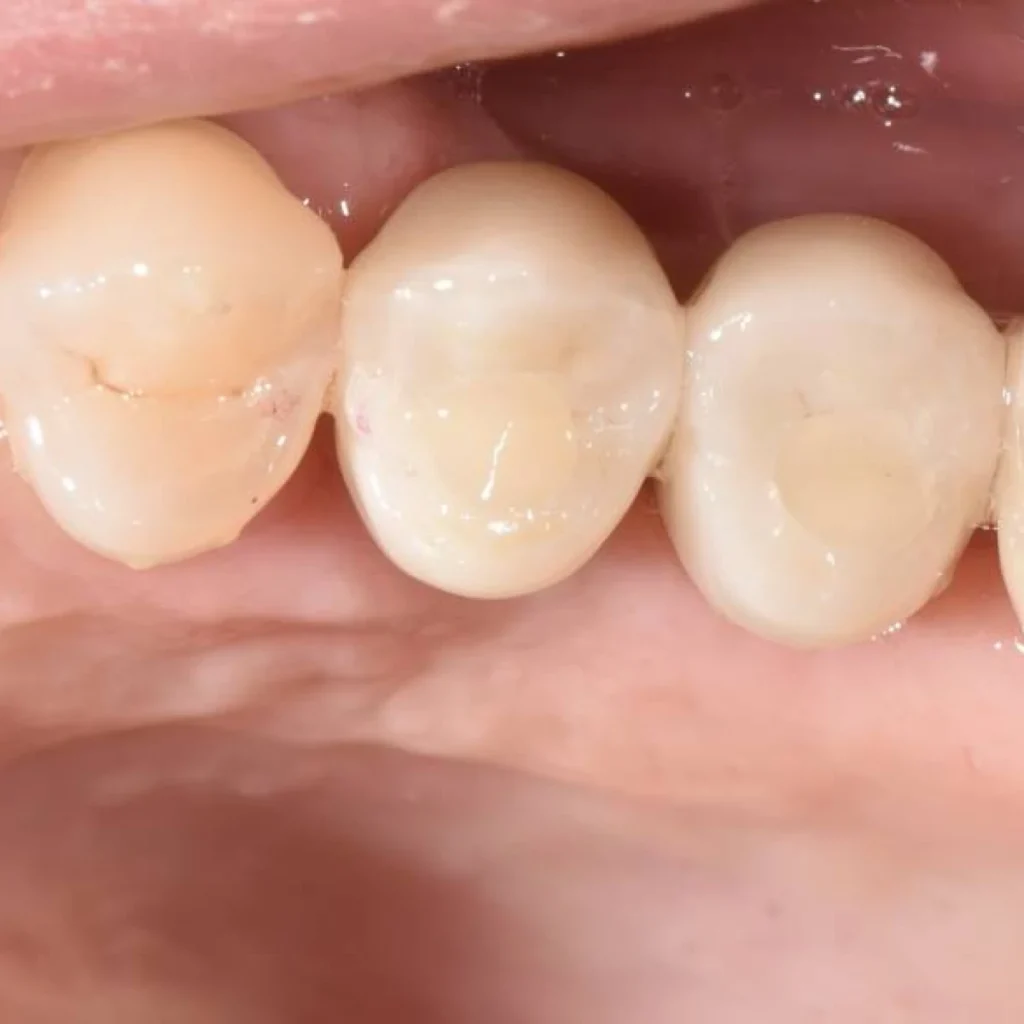

- Une fois les implants posés dans les meilleures conditions, un nouveau temps de cicatrisation de 3 mois est nécessaire à l’intégration des implants.

- Des couronnes tout céramique sont ensuite fixés aux implants.